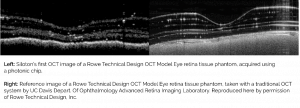

Image of retinal phantom demonstrates capability of Siloton’s photonic chip technology to monitor key parts of the eye affected by macular disease.

Siloton Limited, a trailblazing UK start-up, has acquired a sub-surface image of the retina in a synthetic eye, using its revolutionary photonic chip technology. The synthetic eye, more commonly known as a retinal phantom, is anatomically analogous to a real eye and is used to calibrate clinical devices.

The image was taken with Siloton’s first-generation optical coherence tomography (OCT) chip, Akepa. OCT is a non-invasive imaging technique akin to a high-resolution ultrasound, and is the gold standard for diagnosing and monitoring eye disease. At present, it can only be accessed through hospitals and high-end optometrists, because the optical components inside lead to systems that cost tens of thousands of pounds and take up an entire desk. Akepa compresses a tabletop-worth of heavy, expensive and fragile optical components onto a single piece of material smaller than a £1 coin.

As the first OCT image to be taken with Akepa, this already allows for measurements of retinal layer thicknesses. These are a key marker of disease progression in treatable retinal diseases such as wet age-related macular degeneration, retinal vein occlusion and diabetic macular oedema, all of which affect millions of people worldwide.

Further refinement of the image is ongoing, the results from which will feed into the design of the second-generation Blue Jay chip, as well as Siloton’s wider OCT system.